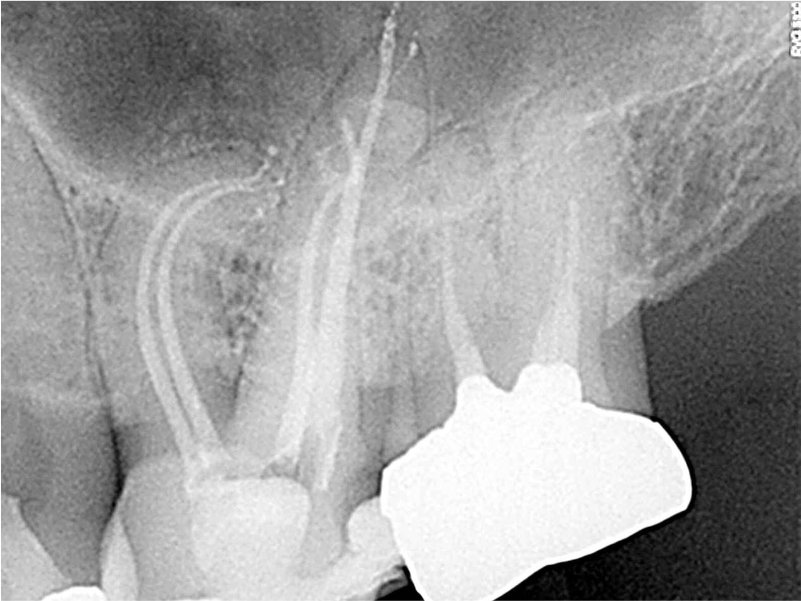

Coronal minimally invasive access.

Buccal canals shaped with Bassi Logic™ 25/.03 and palatal canal with 30/.05.